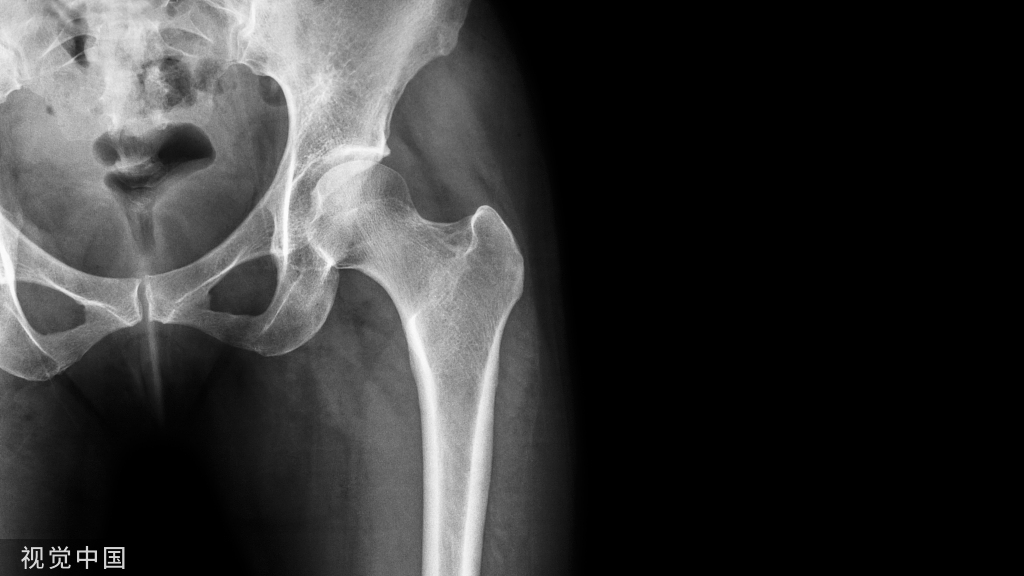

患者,男,71 岁,因右股骨颈骨折入院,既往无高血压、心脏病史,无药物过敏史。术前查体:神志清楚,血压125/85 mmHg ,呼吸20 次/min。ECG示频发性房性早搏。在硬膜外麻醉下行髋关节置换术。

骨水泥植入综合征(bone cement implantation syndrome,BCIS)为骨水泥植入所引起的一系列临床症状,包括低血压、心律失常、严重低氧血症、心肌梗死、肺动脉压(PAP)增高、出血(凝血功能改变)、哮喘发作等。